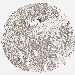

CANCER BREAST CANCER Show tissue menu

BRCA TCGA BRCA VALIDATION PROTEIN EXPRESSION

Breast cancer

Human cancer